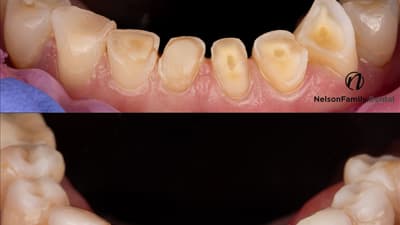

Quantium offers smooth handling without stickiness to the instruments, excellent sculptability, and strong physical properties that support both anterior and posterior applications.

Besides its shade-matching capabilities, OMNICHROMA simplifi es workfl ow, Nelson says, by reducing shade selection, inventory, and what he calls “decision fatigue.”